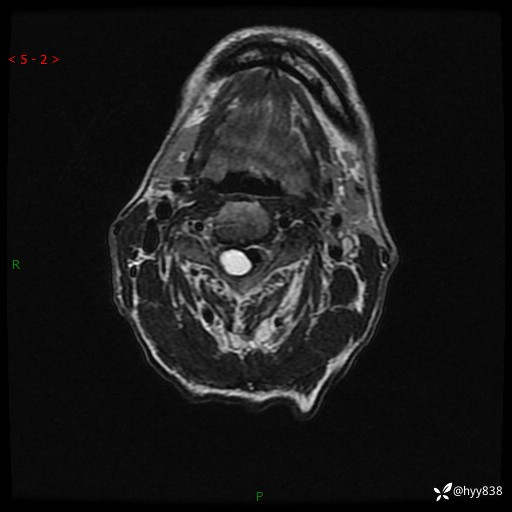

颈椎MRI平扫(sag T1WI+T2WI-fs+axi T2WI)

辅助检查:MRI

临床诊断:椎管占位